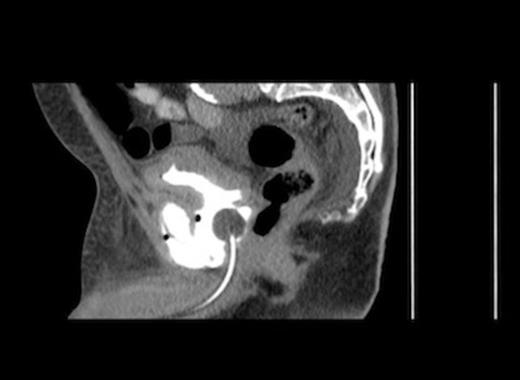

Radiographs confirmed subcutaneous gas associated with the swelling (figure 1). The patient was consented for incision and drainage of the collection, where it was noted that gas bubbles were released on initial stab incision. Copious grey watery fluid was drained from the cavity which appeared to track under the inguinal ligament. Cavity fluid and biopsy specimens were sent for microscopy, culture and sensitivity. The cavity was packed and broad spectrum antibiotics were started following consultation with a microbiologist. A pelvic CT scan with contrast was arranged (figure 2–4), which confirmed a vesicocutaneous fistula.

Figures 2, 3, and 4 are axial, sagittal, and coronal views, respectively, of computed tomography with contrast introduced by urinary catheter. This CT cystogram shows a leak/fistula at the low anterior bladder wall. The fistula has a communication with the pubic symphysis and a collection lies anterior to this. The tract extends distally, communicating with the cavity in the left anteromedial aspect of the thigh.